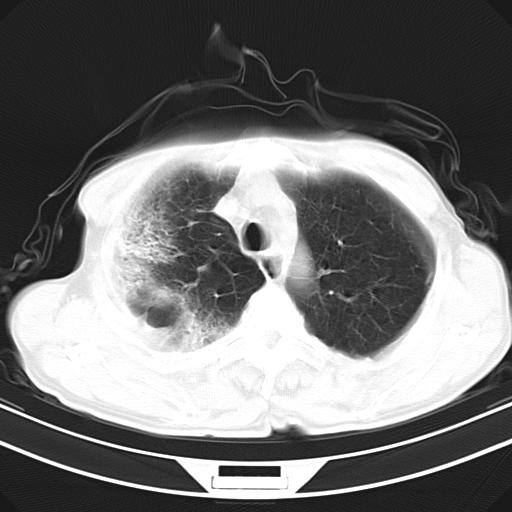

抗炎治疗10天后复查

抗炎治疗10天后复查:右上肺模糊阴影明显减少。

影像所见:右上肺见一巨大厚壁空洞,并见分隔,内壁欠光整,右上肺广泛斑片状、大片状磨玻璃阴影。

诊断意见:考虑右上肺巨大含气囊肿并感染,建议继续治疗后复查。

不支持点:空腔壁较厚,欠光滑。询问病人是否有反复感染病史?

结核临床及影像,结核暂不考虑(十天就明显减轻,不十分支持结核。)